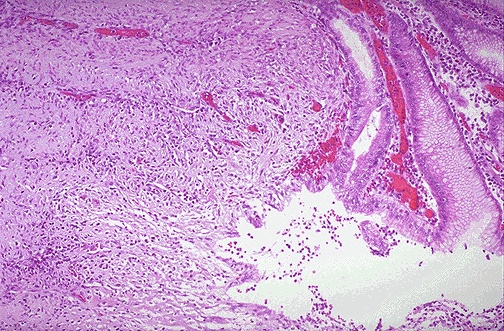

The mucosa at the upper right merges into the ulcer at the left which is eroding through the mucosa. Ulcers will penetrate over time if they do not heal. Penetration leads to pain. If the ulcer penetrates through the muscularis and through adventitia, then the ulcer is said to "perforate" and leads to an acute abdomen. An abdominal radiograph may demonstrate free air with a perforation. |